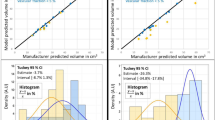

The software-assisted planning of radiofrequency-ablation of liver tumors calls for robust and fast methods to segment the tumor and surrounding vascular structures from clinical data to allow a numerical estimation, whether a complete thermal destruction of the tumor is feasible taking the cooling effect of the vessels into account. As the clinical workflow in radiofrequency-ablation does not allow for time consuming planning procedures, the implementation of robust and fast segmentation algorithms is critical in building a streamlined software application tailored to the clinical needs. To suppress typical artifacts in clinical CT or MRT data - like inhomogeneous background density due to the imaging procedure - a Bayesian background compensation is developed, which subsequently allows a robust segmentation of the vessels by fast threshold based algorithms. The presented Bayesian background compensation has proven to handle a wide range of image perturbances in MRT and CT data and leads to a fast and reliable identification of vascular structures in clinical data.